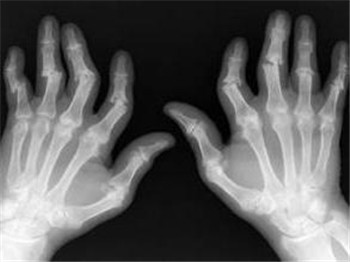

老人经常浑身疼痛是怎么回事?随着年龄的不断增长,很多老年人逐渐出现了浑身疼痛的情况。专家告诉我们,如果浑身疼痛休息后可以缓解,那么就没什么大碍,而如果长时间的出现浑身疼痛现象,就要担心有类风湿性关节炎的可能了。

类风湿关节炎是一种常见的多发病,日常中很多原因都会引发类风湿关节炎,我们一定要多加注意。了解其发病原因对我们预防疾病有很好的帮助,那么导致类风湿性关节炎的原因主要有哪些呢?>>>患上类风湿怎么办?能不能治疗?